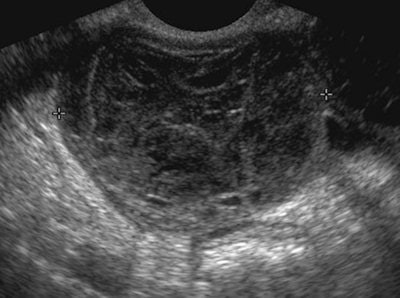

| Although not a typical acute gynecological presentation, this patient presented with abdominal distension, nausea, and vomiting. This transvaginal ultrasound demonstrated symmetric enlargement of the left ovary; however, both ovaries were similar in appearance (often they can be more than 12 cm in size) with multiple cysts of varying sizes. Ovarian hyperstimulation syndrome can also be present with ascites and pleural effusion. Pericardial effusion (due to capillary leak) can also be present. |